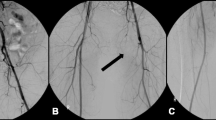

Role of Catheterization Access Routes

Coronary angiography via the femoral artery has been described as the most common precipitating factor in majority of patients with athero-embolic renal disease which may suggest an association regarding catheterization access route [21]. The risk of cholesterol embolization may be potentially increased with the femoral approach due to catheterization of the descending aorta. A prospective study by Kooiman using a regional database compared the risks of acute kidney injury (AKI) and nephropathy requiring dialysis (NRD) among patients treated with transradial percutaneous coronary intervention (PCI) versus transfemoral PCI. In the propensity-matched population consisting of 8857 procedures per group, transradial PCI was associated with lower adjusted odds ratio of acute kidney injury (OR, 0.74; 95% confidence intervals [0.58–0.96]) and bleeding (OR, 0.47; 95% confidence intervals [0.36–0.63]), but no difference in NRD was observed [22].

Similar findings were reported in the Acute Kidney Injury-Minimizing Adverse Haemorrhagic Events by Transradial Access Site and Systemic Implementation of Angiox (AKI-MATRIX) study, a large, randomized, multicenter trial in patients with ST segment or non ST segment elevation myocardial infarction who underwent coronary angiography with or without PCI comparing incidence of AKI with radial versus femoral access. AKI was defined as either an absolute (>0.5 mg/dl) or a relative (>25%) increase from baseline in serum creatinine (sCr) levels during hospitalization. In this study, AKI occurred less in the radial approach compared with the femoral approach (15.4% vs 17.4%, (odds ratio [OR]: 0.87; 95% confidence interval [CI]: 0.77–0.98; p = 0.0181, [23]).

Potential reasons for decreased AKI in the radial approach include decreased risk of cholesterol embolization to the kidneys, decrease in episodes of hypotension due hemodynamically significant bleeding or vasovagal responses to femoral sheath removal, and a lower contrast volumes, although this difference was modest [22, 23]. In contrast, another prospective study by Fukumoto et al. did not find an increased risk of cholesterol embolization syndrome by the femoral approach [10].